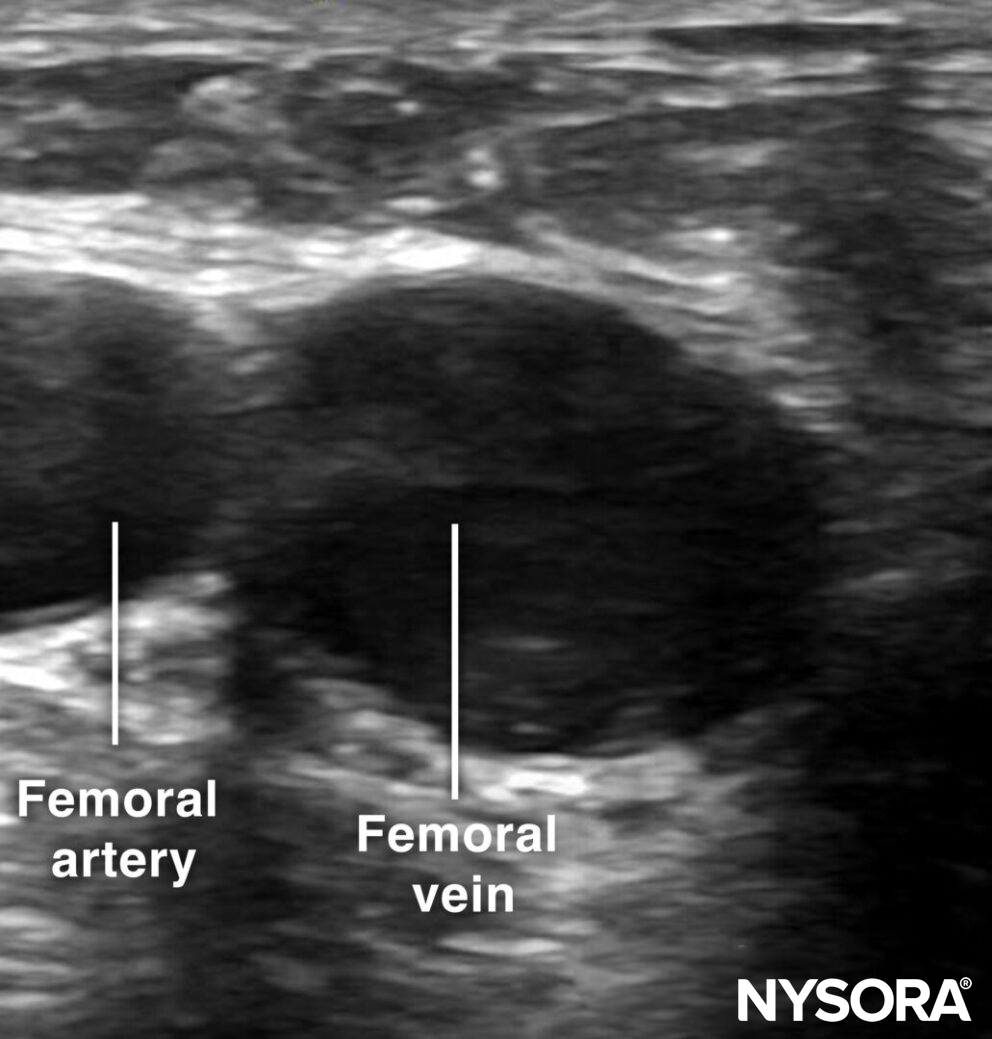

Sonoanatomy for femoral vein cannulation.

The femoral vein is approached just distal to the inguinal ligament by an out-of-plane technique. Use the creep technique to follow the needle tip at all times.